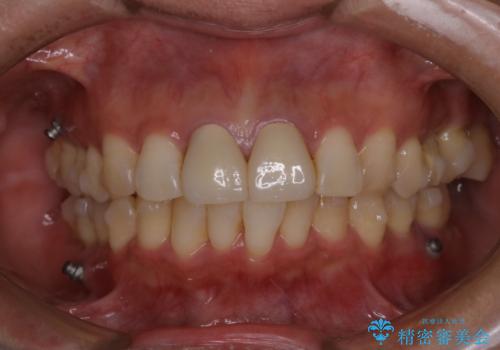

- インビザラインでのマウスピース矯正中の方です。矯正中にも定期的なクリーニングを希望とのことでした。PMTC30分コースを行いました。

マウスピース矯正インビザライン治療では、歯の表面にアタッチメントという突起を設定します。(アタッチメントは歯の動きを効率的に移動するためのものです)

アタッチメントが歯に付くと、表面が凸凹し磨き残しが多くなったりと、プラークや歯石・着色がつきやすくなることがあります。